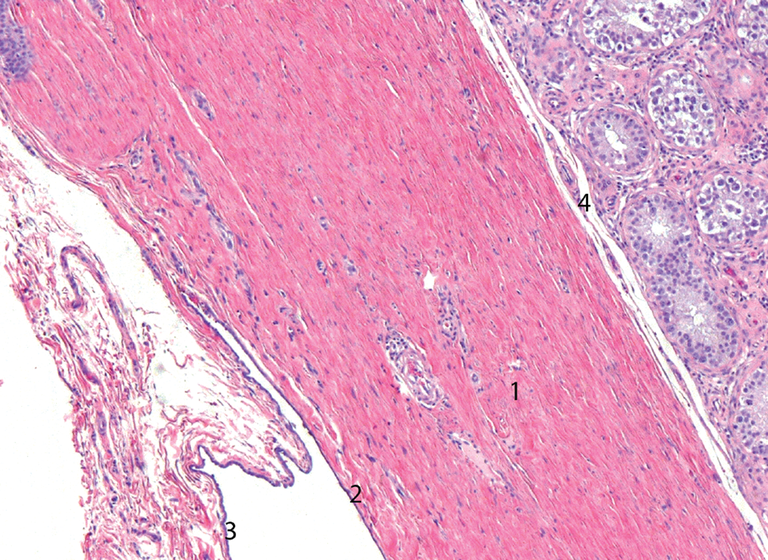

According to researchers at the universities of Porto and Birmingham, the most similar human tissues are the brain and testicles. According to them, although the morphology and functions of these organs are very different, studies of the last 40 waters have shown that they have similarities, for example, in genetic expression: among all the organs of the human body, the most similar in expression are the brain and testicles. The relationship between some sexual dysfunctions and neurological alterations in men has also been suggested. With these evidence, the researchers decided to study the similarities between the brain and testes, and neurons and sperm.

This study analyzed and compared proteins produced by different parts of the body to see similarities. Thus, the greatest similarities were found between the brain and the testicles: 13.442.

Most of the proteins shared by both organs were related to tissue development and communication. As they have explained, this discovery has not been surprising considering that the proteins of both organs consume large amounts of fuel, one to process thought and another to produce millions of sperm. Both are specialized in removing the material they produce: neurotransmitters and sperm.